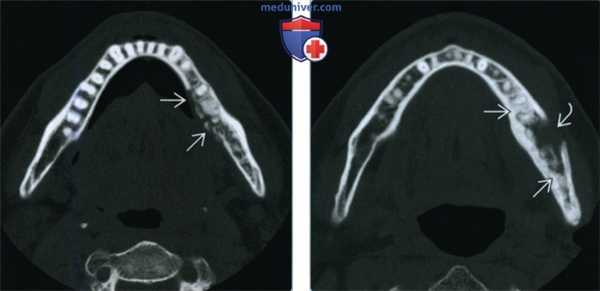

(Слева) На кадрированной панорамной рентгенограмме определяется ОРН в области удаленного третьего моляра. Картина изменений костной ткани смешанная, и включает в себя литический и склеротический компоненты с наличием секвестра. Симптом ступеньки на нижней кортикальной пластинке позволяет предположить патологический перелом.

(Справа) На аксиальной КТ с КУ в костном окне у этого же пациента четче определяются изменения нижней челюсти справа в виде разрежения трабекулярной кости и деструкции кортикальных пластинок. Оаатки кортикальных пластинок секвестрированы. (Слева) На корональной КТ в костном окне у этого же пациента отчетливо определяется фрагментация щечной и язычной кортикальных плааинок наряду с разрежением трабекулярной костной ткани нижней челюсти справа. Также определяется склероз оставшейся губчатой кости.

(Справа) На аксиальной КТ в костном окне у этого же пациента краниальнее определятся более легкие изменения, обусловленные ОРН. Определяется деарукция щечной кортикальной пластинки на уровне нижнечелюстного отверстия. (Слева) На аксиальной КТ с КУ у этого же пациента определяется минимальное утолщение мягких тканей. Уплотнение подкожного жира, утолщение кожи и повышение плотноаи жировых пластинок являются постлучевыми изменениями.

(Слева) На кадрированной панорамной рентгенограмме определяется ОРН в задних отделах нижней челюсти справа после удаления моляра. Выраженная деструкция костной ткани привела к патологическому перелому. Также определяется склероз окружающей костной ткани с наличием секвестра.

(Справа) На аксиальной КТ с КУ в костном окне у этого же пациента определяется патологический перелом нижней челюсти справа с захождением отломков на фоне ОРН. В губчатой кости также визуализируется маленький секвестр. (Слева) На кадрированной панорамной рентгенограмме у этого же пациента 14 месяцев спустя определяется разрешение патологических изменений в нижней челюсти. Имеет место резорбция костной ткани мезиальнее моляра верхней челюсти с разрушением дна верхнечелюстной пазухи, подозрительная на ОРН.

(Справа) На аксиальной КТ с КУ в костном окне у этого же пациента определяется ОРН с поражением нижней челюсти справа. Определяется также деструкция щечной и небной кортикальных пластинок и склероз бугристости верхней челюсти. (Слева) На корональной МРТ (Т1ВИ) у этого же пациента определяется гипоинтенсивный сигнал в костном мозге нижней челюсти справа, обусловленный фиброзом в связи с ОРН. Обратите внимание на нормальный «жировой» сигнал в костном мозге нижней челюсти слева.

(Справа) На корональной MPT (Т2 ВИ FSE) у этого же пациента определяется умеренно интенсивный сигнал в костном мозге нижней челюсти справа, пораженной ОРН. Определяется также легкое повышение интенсивности сигнала в окружающих мягких тканях. Эти изменения также обусловлены вторичным воспалением.